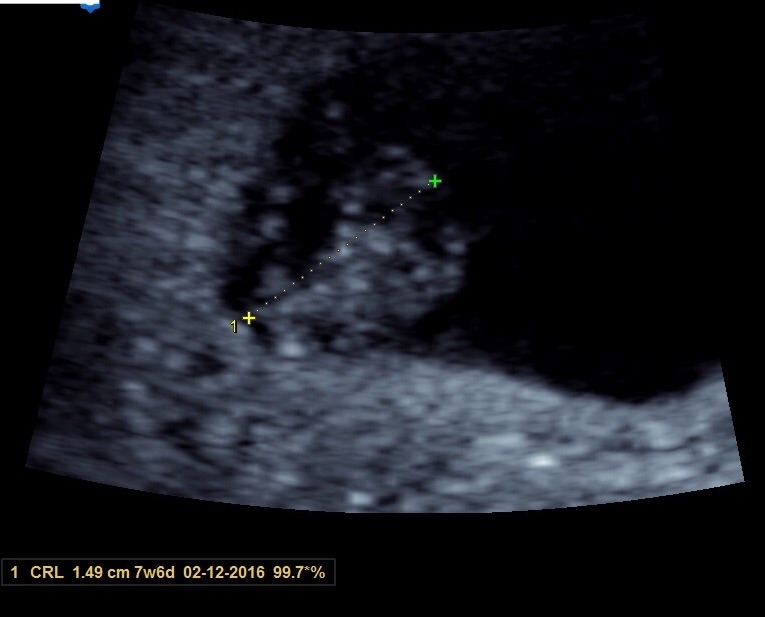

This is my first post, but I am due 2/5/16 with my first little one. Heart rate was 167, and I'm 9w2d right now. US was taken at 8w4d